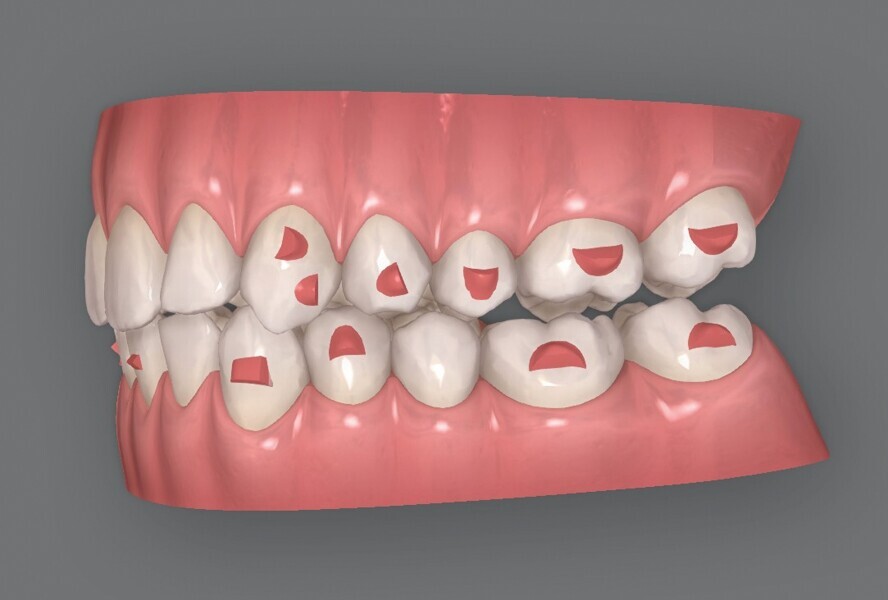

La première série d’aligneurs permet de réaliser les mouvements orthodontiques programmés dans le logiciel avec une efficacité supérieure à 95 % (Fig. 5), et d’obtenir une forme anatomique des arcades, une correction de l’occlusion croisée et de la relation de classe II du côté gauche, une réduction de l’encombrement dans le maxillaire et la mandibule, et un alignement des lignes médianes. Au terme de cette première phase, les observations cliniques indiquent une infraclusion postérieure, résultant de l’intrusion passive des dents postérieures due à l’épaisseur du matériau de l’aligneur, et des contacts antérieurs prématurés. Quelques mouvements dans la zone incisive mandibulaire sont encore nécessaires pour terminer le traitement, et un deuxième jeu d’aligneurs est donc prévu pour éliminer les problèmes et finaliser la position des dents.

Le deuxième plan ClinCheck consiste en 16 aligneurs maxillaires et mandibulaires afin d’effectuer une extrusion des dents postérieures maxillaires et mandibulaires, ainsi qu’une rétraction des incisives mandibulaires de façon à alléger les contacts et fermer l’infraclusion dans la région postérieure. L’accélérateur de traitement par vibrations est toujours utilisé quotidiennement, et l’intervalle de changement des aligneurs est fixé à cinq jours, puis à trois jours par la suite. Les derniers aligneurs ne sont portés que 12 heures par jour afin de permettre la fermeture passive finale de l’infraocclusion postérieure.